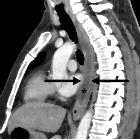

emergencies: another important cause of acute chest pain. Acute esophagitis. Fifty-year-old male with diffuse chest pain and mild fever. Sagittal CT image show diffuse circumferential wall thickening with mild enhancement involving almost entire esophagus (arrows). Intraluminal fluid (asterisk) is noted